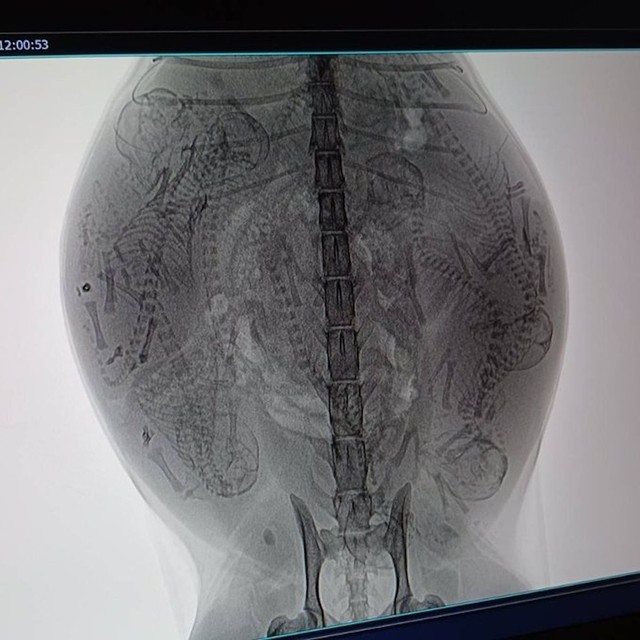

ボランティア仲間に猫の出産に長けた動物病院を紹介してもらい、威嚇する母猫を連れていくと、母猫は推定2~3歳で、体内には「8匹」の子猫がいることが判明した。